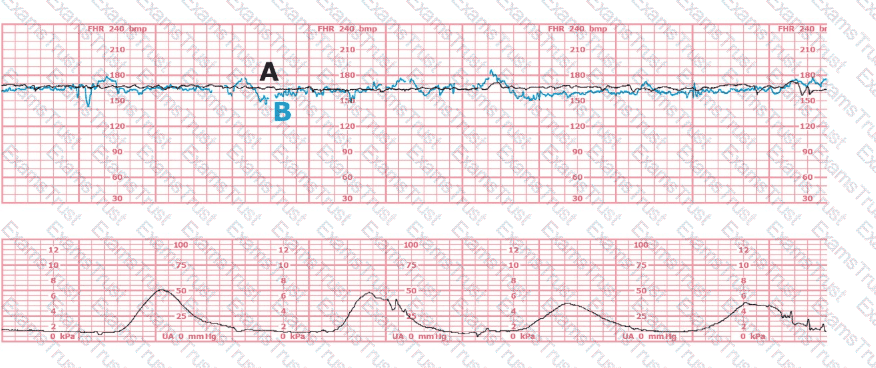

This fetal heart rate tracing is of a woman in labor with dichorionic-diamniotic twins at 36-weeks gestation, 4 cm dilated. She is on oxygen via face mask. Based on the fetal heart rate tracing, what is the most appropriate action?

(Tracing A = black; Tracing B = blue)

The black pattern represents the heart rate pattern for Baby A. The blue pattern represents the heart rate pattern for Baby B. A possible etiology of the baseline fetal heart rate of Baby A is: